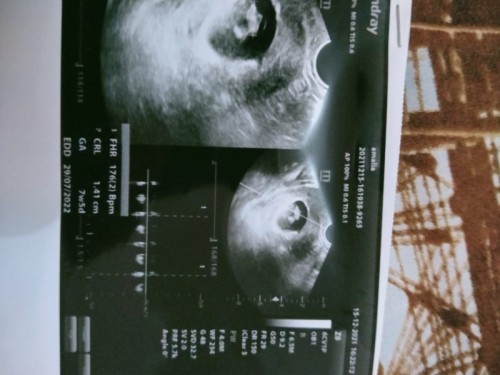

Bunda aku hamil masuk 8minggu1hari,jika mau usg yang ketauan jenis kelamin nyadi usia kandungan brp

Ingin tau jenis kelamin di usia kandungan brp?

Kalau mau liat jenis kelaminnya di usia 20 minggu ke atas bund, Insyaallah udah keliatan tpi tergantung posisi adeknya juga nutupin atau enggak. Kalau saya pernah USG di 15 minggu, kata dokter udh keliatan cuma masih prediksi soalnya posisi bayi agak nutupin. Jadi masih prediksi sementaranya itu, saya disarankan lagi USG di 20 minggu ke atas aja biar jelas kata dokter. Tpi sekrang blm USG lagi pdahal udh 22 minggu, soalnya RS jauh sekali dri tempat tinggal suami.

Baca lagi16w biasanya udh bisa ktauan JK nya, aplgi klo posisi debay mndukung. tp klo aku sndri lebih pnting si debay nya ktauan sehat, posisi baby sm plasenta bagus bun. klo JK nya blm ktauan bisa di coba lgi liatnya buln brikutnya ๐๐ ank prtma uk 28w ktauan JK nya. ank kdua uk 21w udh ktauan JKnya to ๐ค

skrg usia kemahilanku udh 23 week dan kemarin aku di USG pengin tau jenis kelaminnya apa,ehh pas diusg si anaknya mlah gk ngangkang jdi gk kliatan๐ . tpi alhamdulilah sianaknya baik" aja bb nya stngah kilo dan posisi kepalanya udh dibawah ๐๐

bu ibu usg itu gunanya bukan cuma liat jenis kelamin aja bu. jk nampak jika kehamilan sudah memasuki 18w bu. yg terpenting itu bbjanin, air ketuban dll bu

kmrn saya dari 12wk sudah kliatan dan di perkirkan oleh dokter.. dan di pastikan kmbli pas usia 18wk trnyata bnr perkiraan nyaa

aku USG penasaran pas di 18minggu tapi ga keliatan pas kmren di USG lagi di 20minggu eh kliatan cewek Alhamdulillah ๐ค